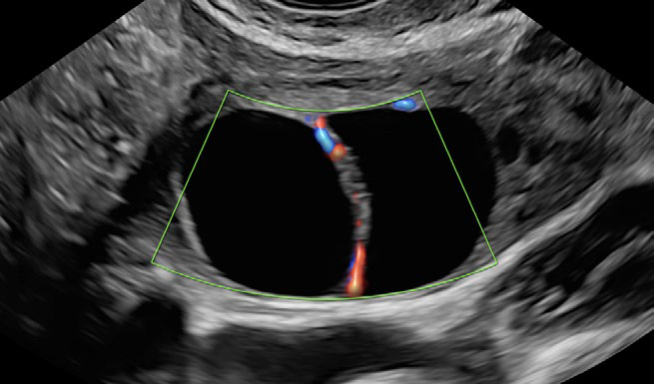

• RadiantflowTM

Calidad de color mejorada y mayor sensibilidad

Separación mejorada entre vasos sanguíneos que proporciona la percepción de un flujo sanguíneo dinámico, añade información de altura y profundidad para una apariencia 3D, Menos destellos, límites vasculares mejorados e Identificación fácil y rápida incluso de los vasos más pequeños.